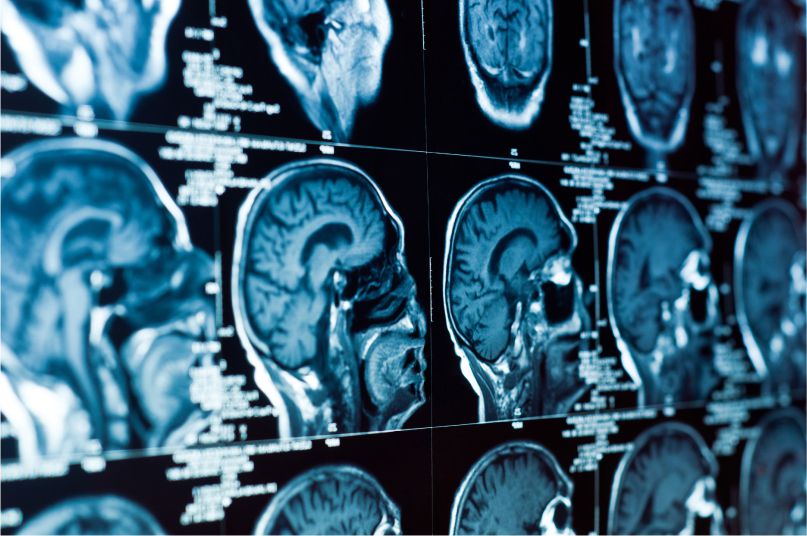

One such study, from the Institute for Learning and Brain Sciences at University of Washington (UW), examined growth in reading skills and white matter in school-aged, struggling readers. Diffusion MRI data collected during eight weeks of Lindamood-Bell® intensive instruction using the Seeing Stars program indicates that there were large-scale changes in white matter along with growth in reading skills. Additionally, the study identifies white matter tracts that may predict the ease with which a child learns how to read.

The study focused on three areas of white matter—regions rich with neural connections—that link regions of the brain involved in language and vision. After eight weeks of intensive instruction among study participants, two of the three areas of white matter showed evidence of structural changes—a greater density and more organized “wiring.” That plasticity points to changes brought about by the environment, indicating that they are flexible structures that reorganize in response to experiences children have in the classroom or during intervention.

Dr. Jason Yeatman, one of the study’s researchers, says that, "While many parents and teachers might worry that dyslexia is permanent, reflecting intrinsic deficits in the brain, these findings demonstrate that targeted, intensive reading programs not only lead to substantial improvements in reading skills, but also change the underlying wiring of the brain’s reading circuitry.”